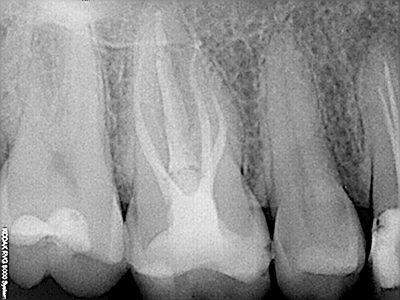

NUESTROS CASOS:

Endodoncia

Capielo